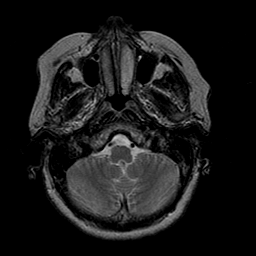

Stroke:T2-weighted MR #1 -- Slice #3

[Home][Help][Clinical] Slice 3